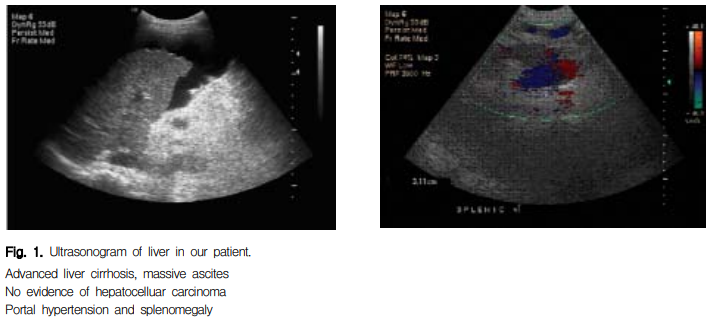

입원 당시 혈액검사 소견 : 혈색소 10.0 g/dL, 백혈구 3700/mm3 , 혈소판 60000/mm3으로 빈혈, 혈소판 감소증 및 경도의 백혈구 감소증 소견이 관찰되었고, 혈액응고 검사는 PT (prothrombin time 프로트롬빈 시간) 1.31 INR, aPTT (activated partial prothrombin time 활성 부분 트롬보플라스틴 시간) 35.3초로 정상이었다. 간효소치는 AST (Aspartate aminotransferase 이하 AST) 121 IU/L, ALT (Alanine aminotransferase 이하 ALT) 74 IU/L, 총 빌리루빈 3.0 mg/dL, alkaline phosphatase 114 IU/L, 혈장 알부민 2.2 g/dL이었다(Table 1). 이상의 혈액소견 및 이학적 관찰상 Child pugh class type B의 간경변으로 진단하였다. 혈액형은 Rh양성 B형이었고 소변검사에서는 단백+1양성 이외 특이소견은 없었다. 혈청 매독검사 (VDRL) 음성, B형간 염 바이러스 표면항원 (HBs antigen) 양성, B형간염 바이러스 표면항체 (HBs antigen)는 음성, HBe 항원 음성, HBe 항체 양성, HBS DNA는 음성이었다. 흉부 X-선에서 약간의 심비대를 보였으나 정상 폐소견, 심전도는 정상이었다. 간 초음파상 진행된 간경변, 다량의 복수, 문맥압 항진증, 비장비대가 보였으나 간암의 증거는 없었다(Fig. 1). 1년 전에 시행한 위 식도내시경 상 식도정맥류 소견은 보이지 않았다고 하였으며, 간 생검은 시행한 적 없었다.